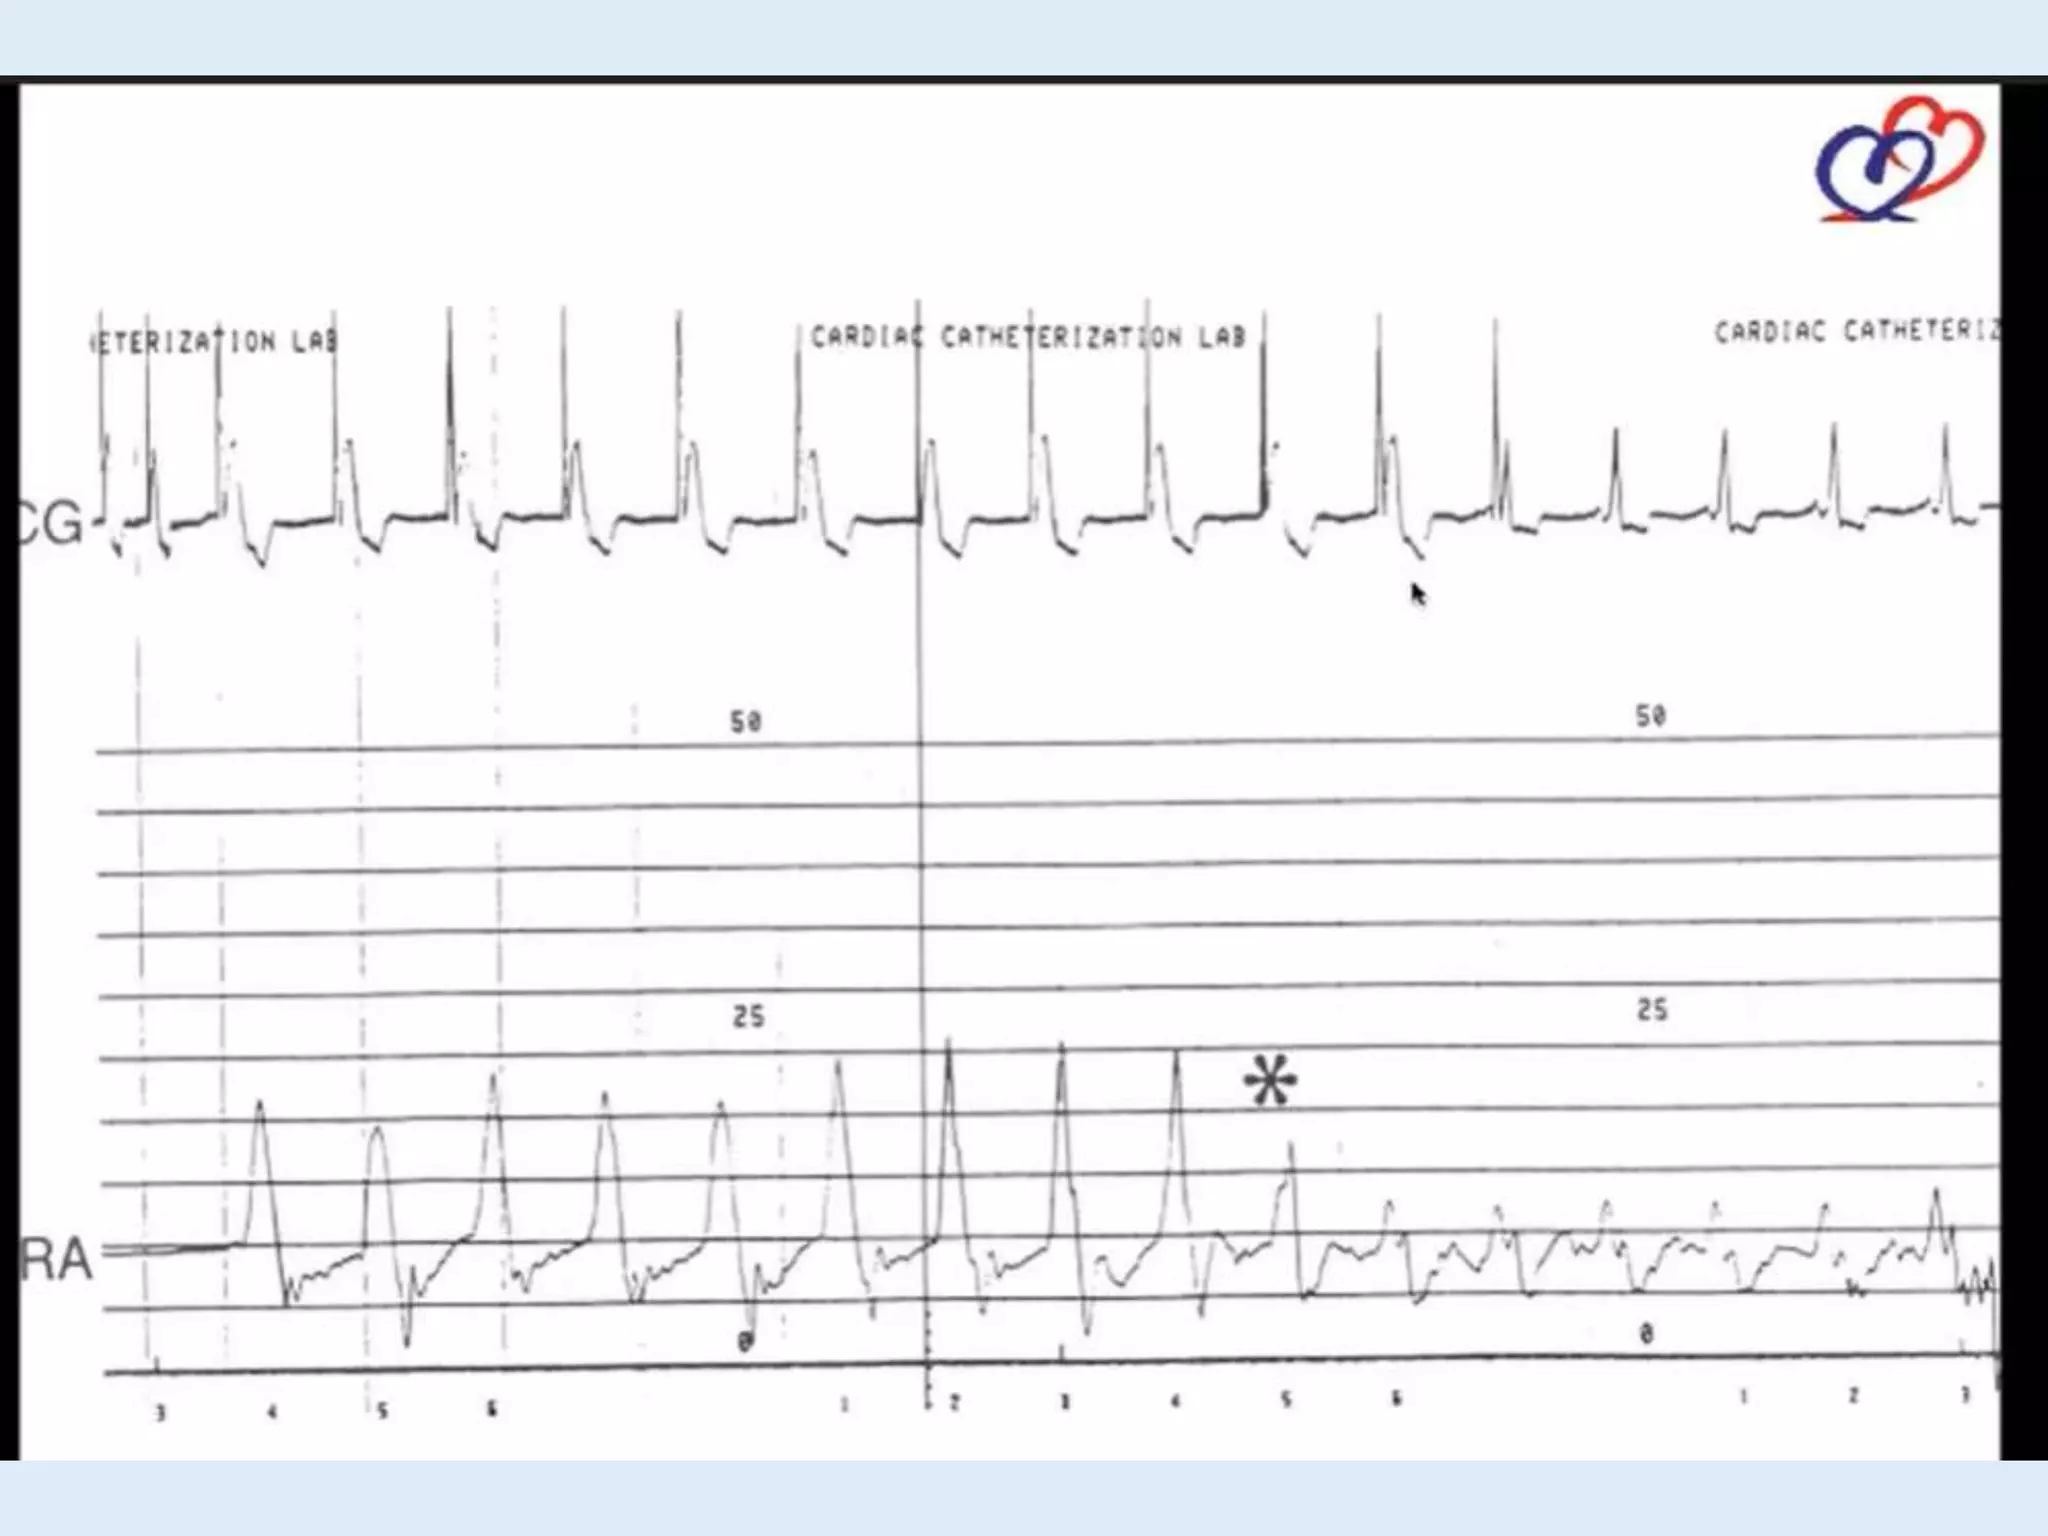

This document discusses right heart catheterization and the interpretation of pressure wave tracings from such a procedure. It notes that in a normal patient, right atrial and right ventricular pressure tracings will show smooth waves ranging and overshooting the right ventricular pressure. The tracing clearly shows the a wave of atrial contraction and the c wave of ventricular filling. It concludes by thanking the reader.